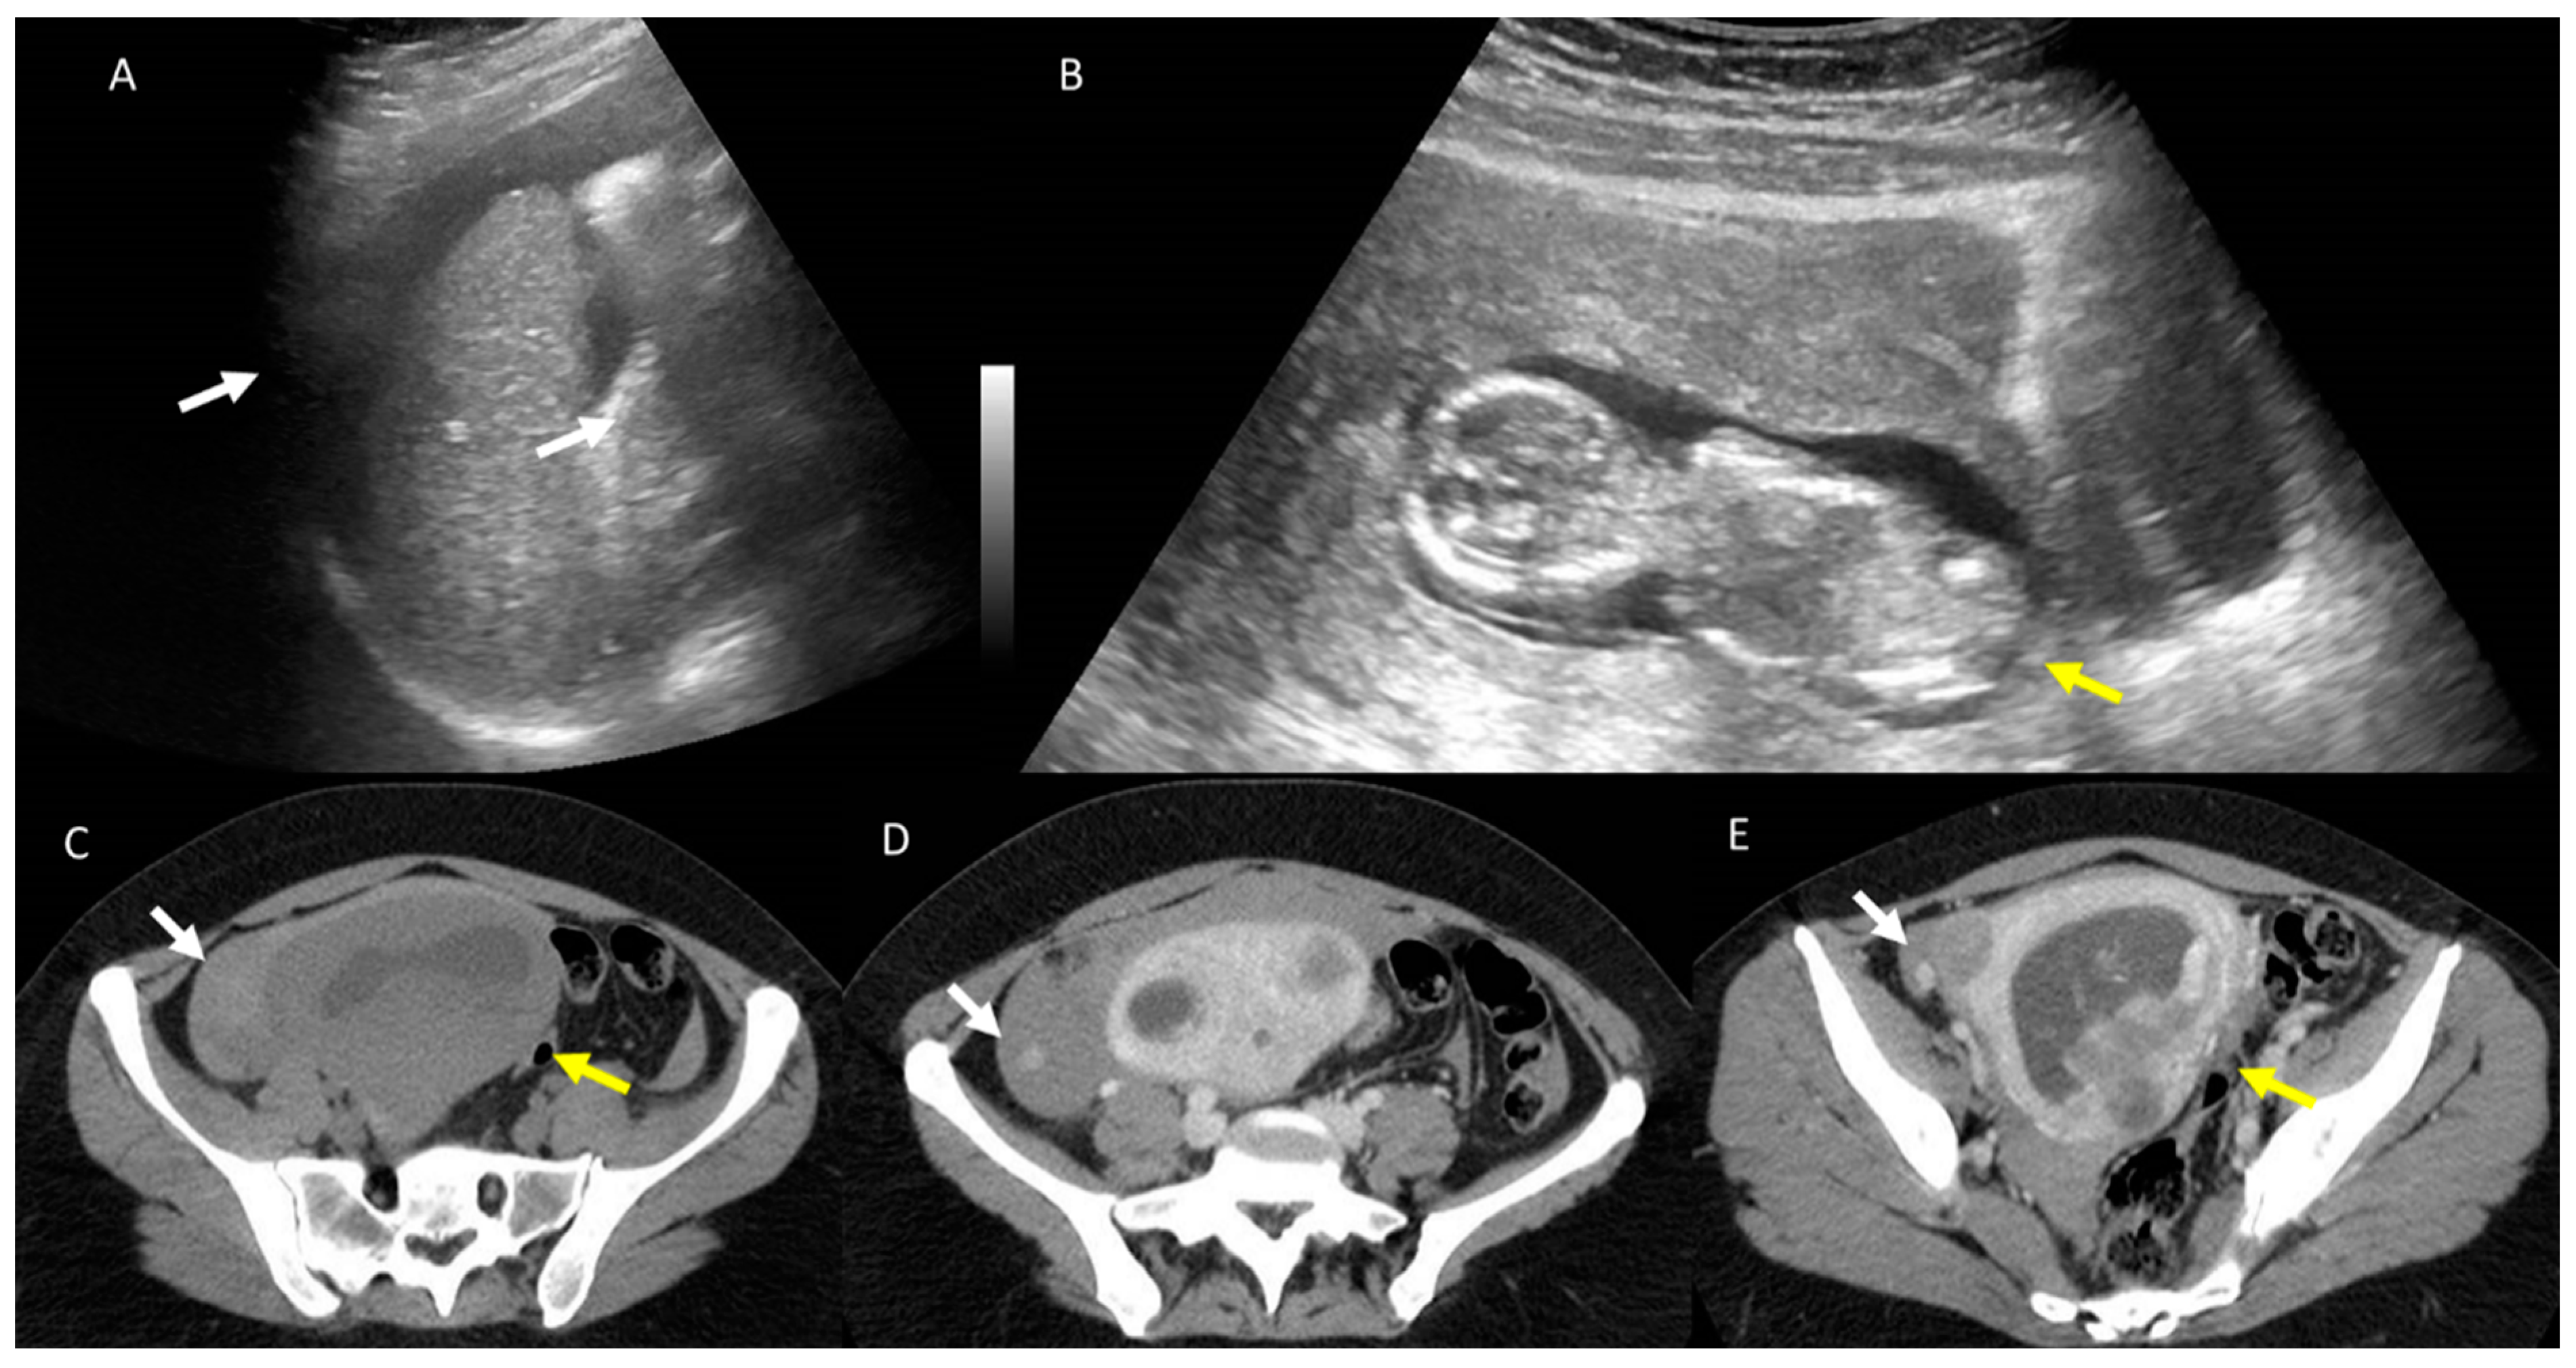

Figure 6.

Polytraumatized (crash accident) pregnant woman (yellow arrows) admitted to emergency room. Fast US (A and B) shows abdominal free fluid. Unenhanced CT (C), white arrow shows intraabdominal blood with active bleeding (white arrows in D,E) after contrast medium administration.